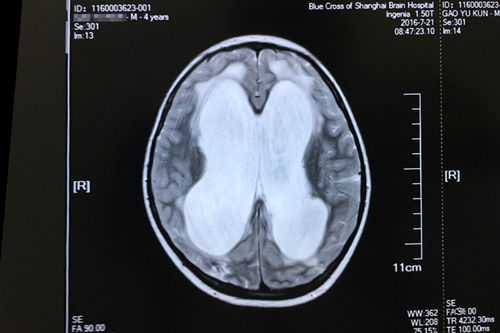

車禍昏迷74天后,亮亮來到了“藍(lán)十字”。完善相關(guān)檢查之后,神經(jīng)外科主任侯增欣(政府特殊津貼專家)、原上海復(fù)旦大學(xué)附屬華山醫(yī)院神經(jīng)外科專家潘仁龍主任,以及亮亮的主治醫(yī)生副主任醫(yī)師經(jīng)過病情討論會診之后,給亮亮下的結(jié)論是:重型顱腦損傷、化膿性腦膜炎、腦積水、多發(fā)性骨折。侯增欣主任和其他專家一致認(rèn)為:雖然亮亮的傷情嚴(yán)重,但治療的希望還是有的。頭顱MR顯示:腦積水明確,各項(xiàng)檢查完善,未見明顯手術(shù)禁忌,可以開展“腦室-腹腔分流術(shù)”。

亮亮術(shù)前的磁共振影像顯示:重度腦積水伴間質(zhì)性腦水腫